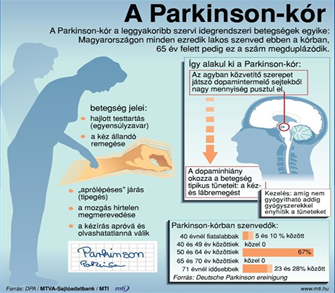

• Parkinson kór tünetei, orvosi, gyógyszeres és alternatív (NADH, kannabisz) kezelése